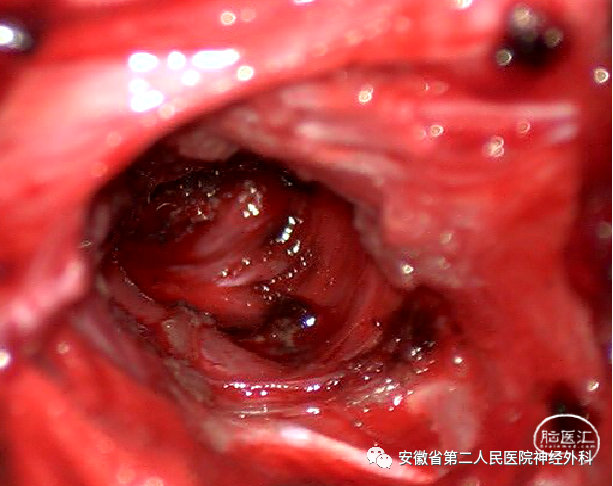

后正中半椎板入路切除神经根处肿瘤,探查松解神经根出椎间孔处